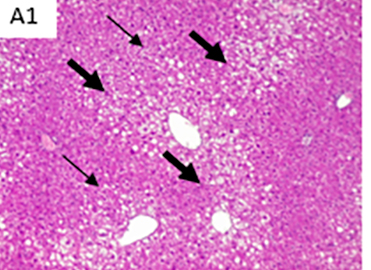

Fotografías a cortes histológicos de hígado, después de 12 semanas, parte de ensayo preclínico: CD: dieta control; HFD: dieta alta en grasa; A1: dieta alta en grasa + concentrado Omega-3 pescado; y A4: dieta alta en grasa + lípidos terapéuticos Nutri-Omics. Flechas muestran los distintos niveles de gravedad de los focos de esteatosis macro y micro vesicular después de ser sometidos a una dieta alta en grasa.